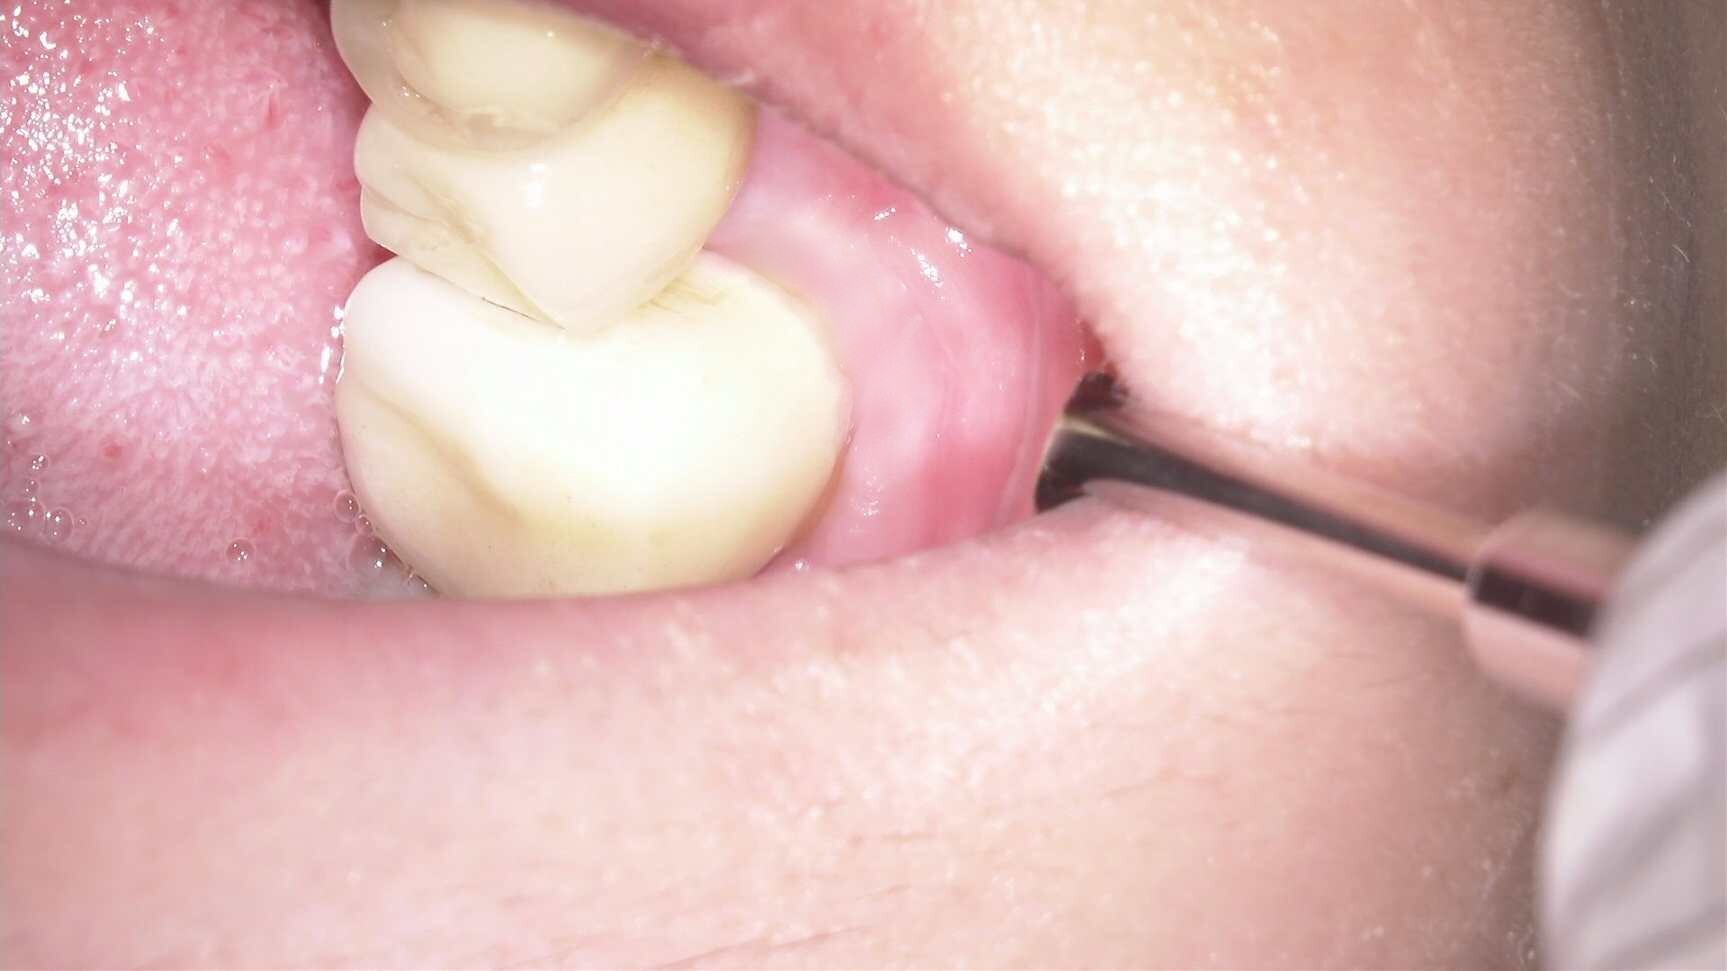

| 主訴 | 歯を白くしたいため来院。 |

| 治療内容 | オフィスホワイトニングを1セット(フッ素塗布、薬剤3回塗布×2日)を行いました。 |

歯の黄ばみが気になる方へおすすめです。

しみる症状が出にくいように処置の前後でフッ素の塗布を行っています。